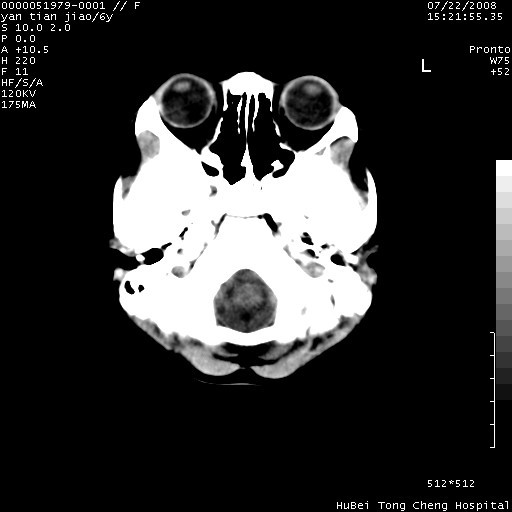

患儿 女,6岁。发热三天,昏迷五小时伴抽搐一次入院。pe:神志不清,浅昏迷状,双侧瞳孔不等大(右侧瞳孔直径3.5mm,左侧瞳孔2.0mm),对光反射迟钝,项强约一指,脑膜刺激征及病理反射阳性;双肺可及痰鸣音;四肢肌张力不高。

临床诊断:病毒性脑膜脑炎并脑疝?

颅脑ct轴位平扫,如下图:

大面积低密度区,可疑脑炎,建议强化!

结合临床症状,符合右颞顶枕叶病毒性脑膜脑炎.建议增强或mri。

右侧低密度区结合临床考虑脑炎